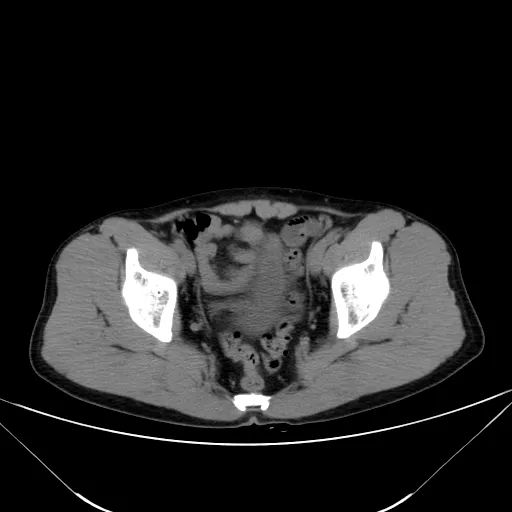

5.双肾位置,大小,密度,周围,集合系统,然后连续看双输尿管及膀胱

6.子宫及附件,前列腺及精囊腺,尿道